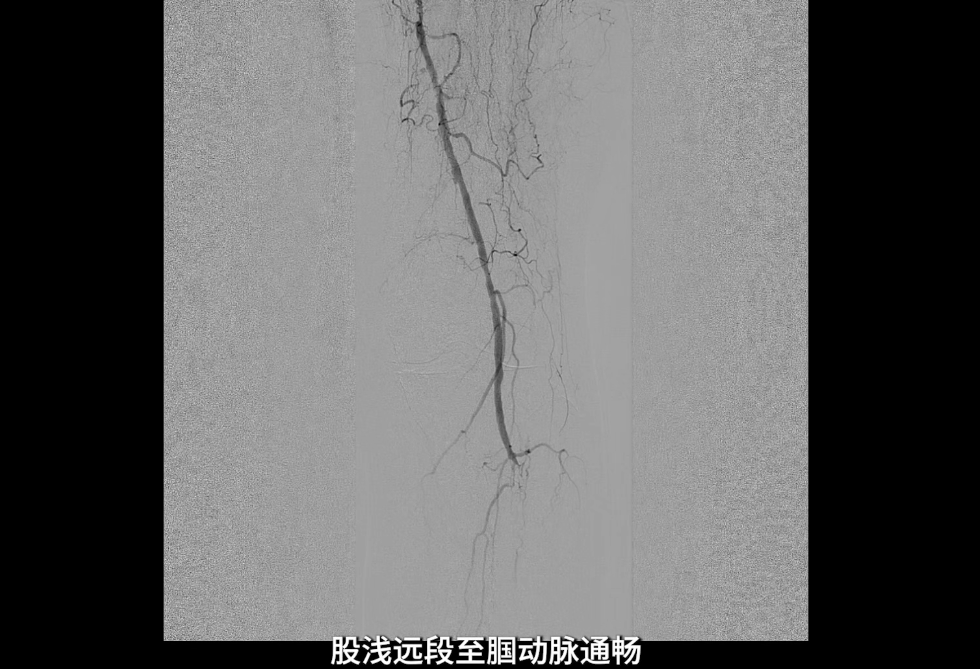

术中造影确认病变

左侧股浅动脉中上段明确长段狭窄并闭塞,病变长度约15cm,股浅动脉远段至腘动脉管腔通畅。

膝下动脉三支主干均闭塞,胫后动脉远端经侧支循环显影;腓动脉远端为“休眠血管”,通过与胫后动脉的交通支实现逆向显影。